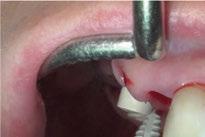

y lo que se pudo preservar del hueso malar. Se añadió una malla sinterizada infraorbitaria para dar volumen a la mejilla y se planificaron dos brazos de conexión que emergieran en las posiciones 24 y 26 de forma subgingival (Figuras 8 y 9). La superficie interna que apoyaba en el hueso era de titanio microrrugoso, y la superficie externa y conectores de titanio pulido y hexágono externo universal (Figuras 10 y 11). La cirugía se hizo bajo anestesia general en infiltración con anestesia local (4% articaína, 1:100.00 epinefrina), levantando el

colgajo cutáneo de la mejilla por vía intraoral, preservando el colgajo temporal para no comunicar con el remanente de la cavidad naso maxilar (Figura 12). Se emplearon 10 tornillos de osteosíntesis de 1,9 mm y la estabilidad primaria obtenida fue excelente (Figura 13)

Figura 13. Fijación del implante y emergencia de las conexiones.